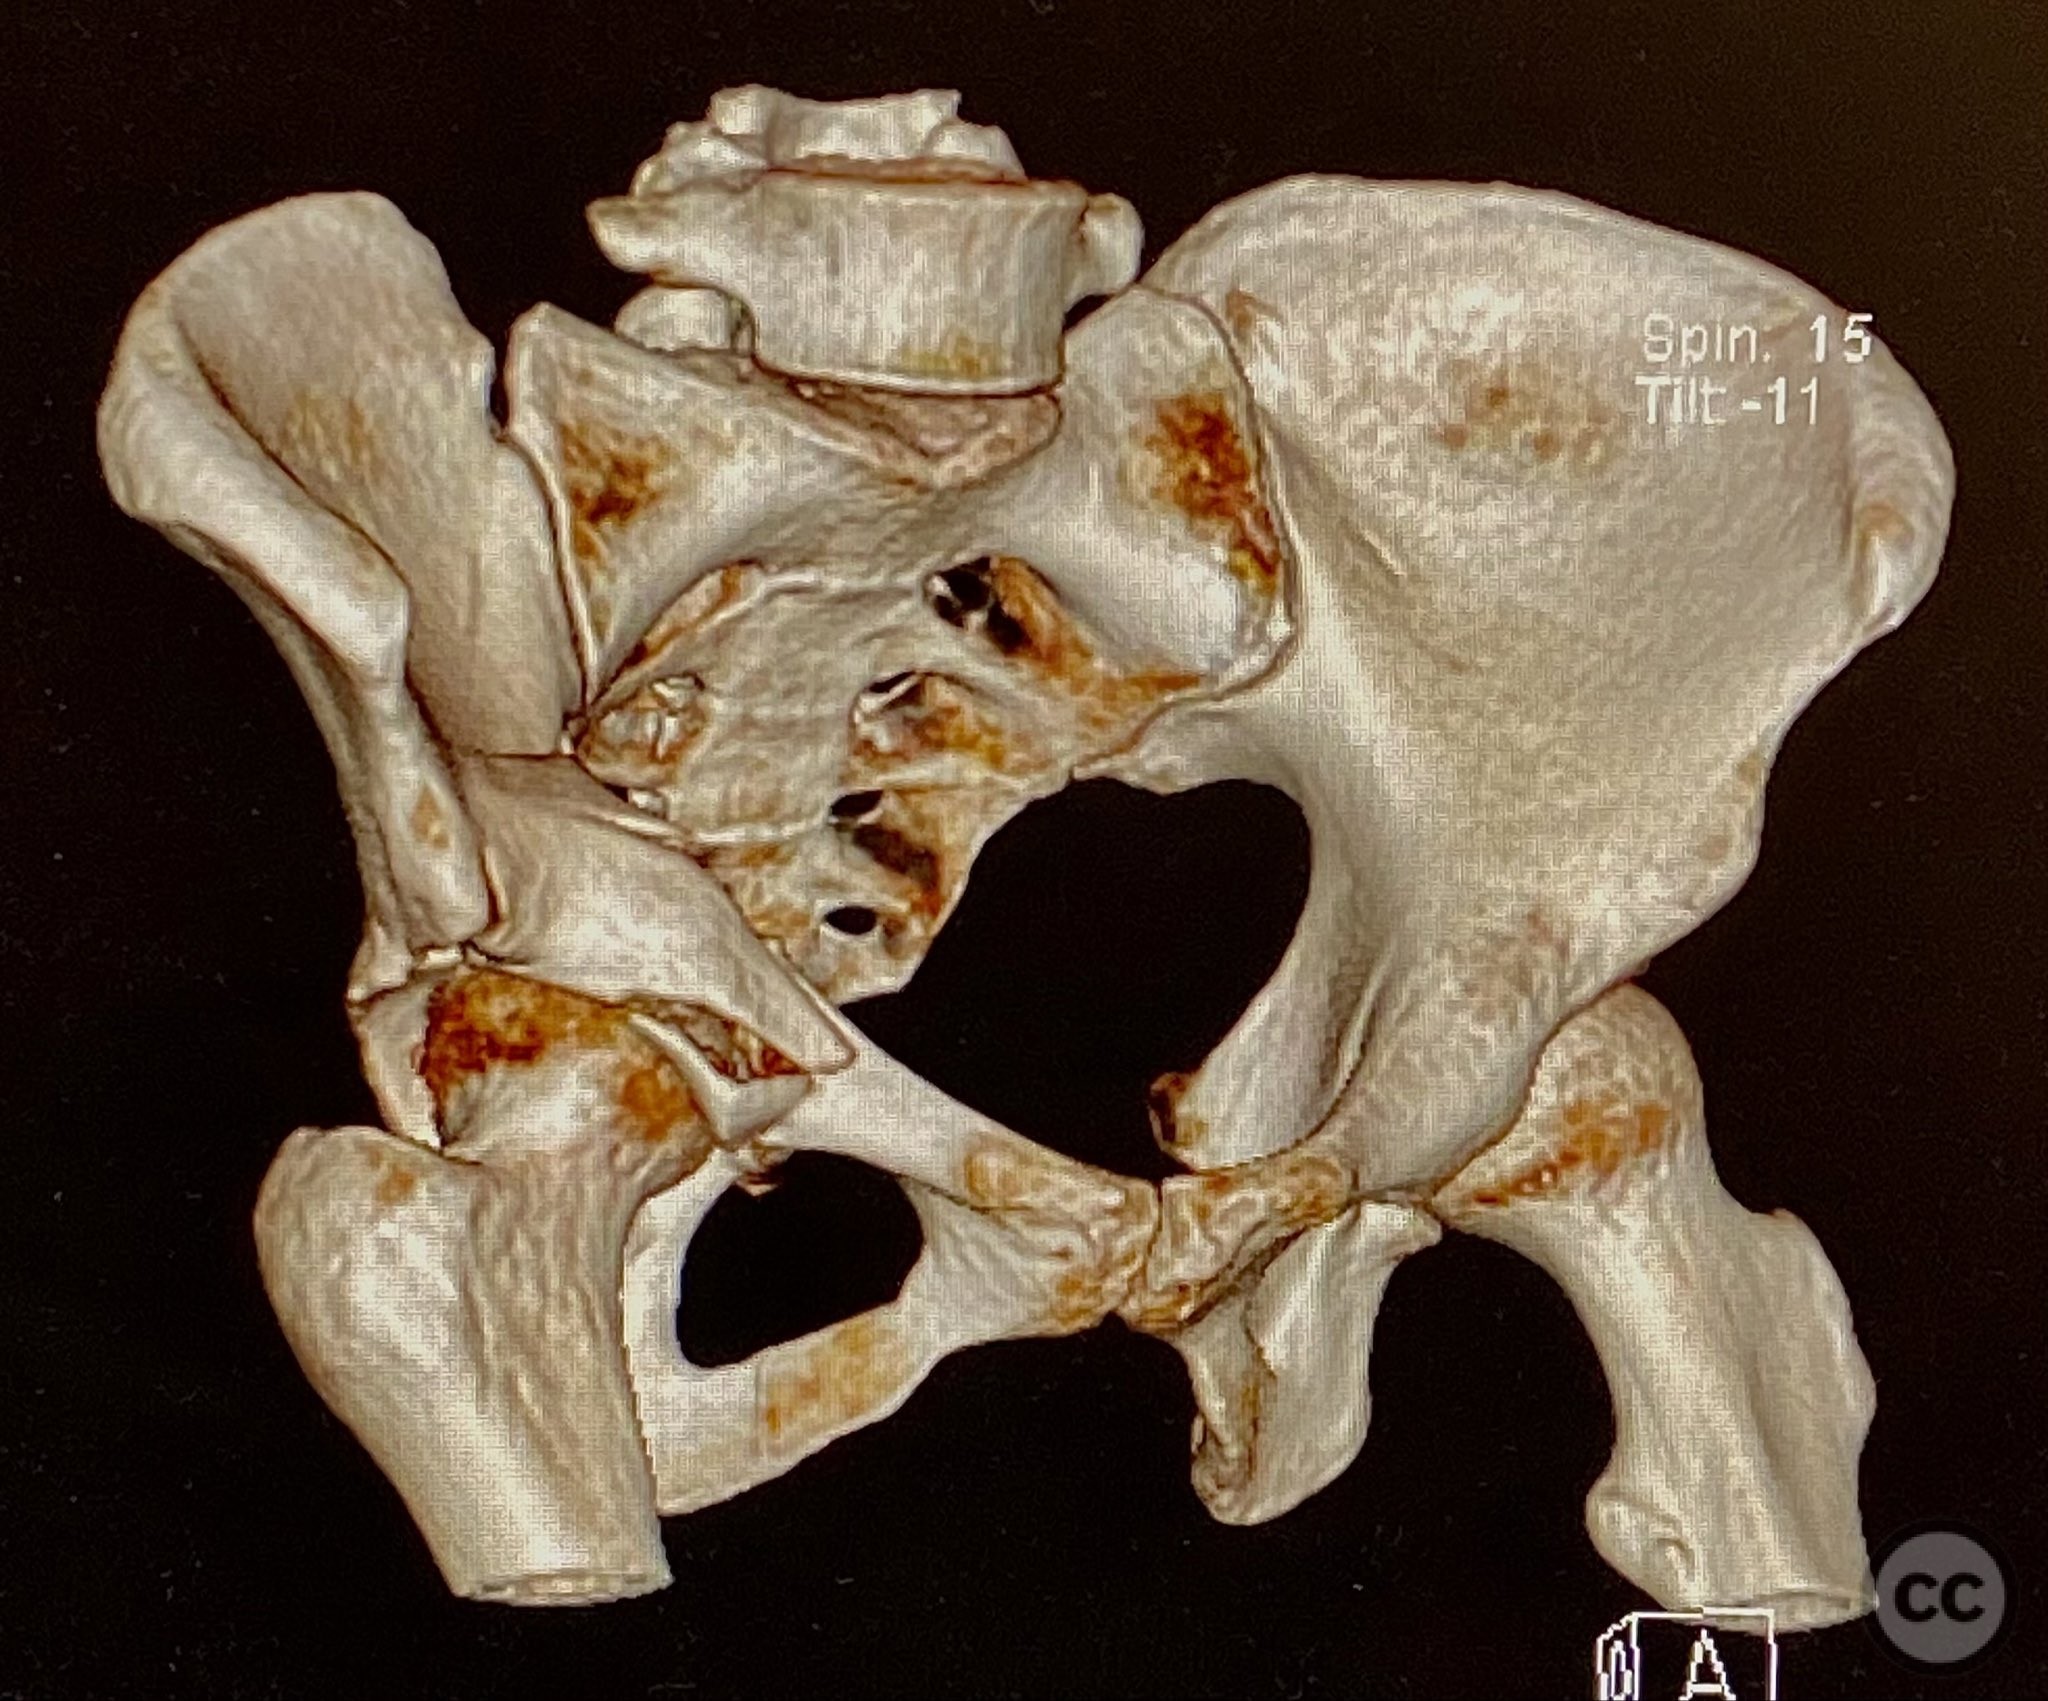

Clinical and radiological findings:  The patient sustained an acetabular fracture with a rare posterior medial dome impaction fragment, as demonstrated on AP pelvic radiographs obtained in skeletal traction. Surface renderings and axial CT images revealed multiple incomplete fracture lines, including a rhomboid-shaped cortical fragment adjacent and proximal to the anterior column/wall fragment. Coronal and sagittal reconstructions further delineated the impacted articular fragment and its relationship to the surrounding acetabular dome. The fracture pattern is classified as AO/OTA 62B3 (associated both-column fracture with dome impaction).